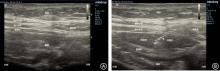

目的 探讨弓状韧带上腰方肌阻滞(QLB-LSAL)与肋缘下腹横肌平面阻滞(STAPB)对腹腔镜结直肠癌根治患者围术期镇痛及术后炎症的影响。 方法 纳入2022年10月至2024年10月择期全麻下行腹腔镜结直肠癌根治术患者102例,两组均行全麻联合神经阻滞,根据神经阻滞方式随机分为弓状韧带上腰方肌阻滞组(Q组,n = 51)和肋缘下腹横肌平面阻滞组(S组,n = 51)。记录麻醉诱导前(T0)、手术开始前(T1)、手术开始时(T2)、人工气腹时(T3)、腹腔冲洗时(T4)、手术结束时(T5)、出手术室时(T6)的平均动脉压(MAP)及心率(HR);记录瑞芬太尼、镇痛泵使用及补救镇痛情况;记录术后24、48及72 h静息及咳嗽时的VAS评分;记录术前1 d、术后1 d及3 d的白细胞介素-6(IL-6)及系统免疫炎症指数(SII);记录术后恢复及不良反应发生情况。 结果 Q组在T3 ~ T6时MAP及HR低于S组(P < 0.05);与S组比较,Q组瑞芬太尼用量减少、镇痛泵首次按压时间延长、有效按压次数及补救镇痛例数更少,术后24 h和48 h静息及咳嗽时VAS评分更低(P < 0.05);与术前1 d比较,两组术后1 d及3 d的IL-6及SII均升高,但Q组低于S组(P < 0.05);与S组比较,Q组首次下床时间及术后住院时间更短,不良反应发生率更低(P < 0.05)。 结论 QLB-LSAL较STAPB可为腹腔镜结直肠癌根治术患者提供更好的围术期镇痛,降低炎症反应,加速术后恢复。

Objective To compare the effects of quadratus lumborum block at the lateral supra-arcuate ligament (QLB-LSAL) versus subcostal transversus abdominis plane block (STAPB) on perioperative analgesia and postoperative inflammation in patients undergoing laparoscopic radical resection of colorectal cancer. Methods In this prospective randomized study, we recruited 102 patients undergoing laparoscopic colorectal cancer surgery between October 2022 and October 2024 under general anesthesia and randomly assigned them to two groups: QLB-LSAL (Group Q, n = 51) and STAPB (Group S, n = 51). Mean arterial pressure (MAP) and heart rate (HR) were recorded before anesthesia induction (T0), before surgical incision (T1), start of surgery (T2), during pneumoperitoneum establishment (T3), during peritoneal lavage (T4), at the end of surgery (T5), and upon leaving the operating room (T6). Intraoperative remifentanil consumption, time to first patient-controlled analgesia demand, and frequency of effective compression and rescue analgesia were recorded. Visual Analog Scale (VAS) scores at rest and during coughing were assessed at 24, 48, and 72 hours postoperatively. Interleukin-6 (IL-6) and systemic immune-inflammatory index (SII) at 1 day preoperatively, 1, and 3 days postoperatively were recorded. Postoperative recovery indicators and adverse events were also recorded. Results Group Q demonstrated significantly lower MAP and HR compared with Group S from T3 to T6P < 0.05). Group Q had significantly lower intraoperative remifentanil consumption, significantly longer time to first analgesic pump demand, fewer effective pump compression, and lower frequency for rescue analgesia requests (all P < 0.05). VAS scores at rest and during coughing in Group Q were significantly lower at 24 h and 48 h postoperatively (P < 0.05). As compared with preoperative levels, both IL-6 and SII increased at 1 and 3 days postoperatively, but magnitude of increase in Group Q was smaller than in Group S (P < 0.05). In comparison to Group S, Group Q demonstrated significantly earlier ambulation, shorter hospital stay, and fewer adverse events (P < 0.05). Conclusion QLB-LSAL is superior to STAPB in enhancing perioperative analgesia, attenuating inflammatory response, and accelerating postoperative rehabilitation in patients undergoing laparoscopic colorectal cancer resection.